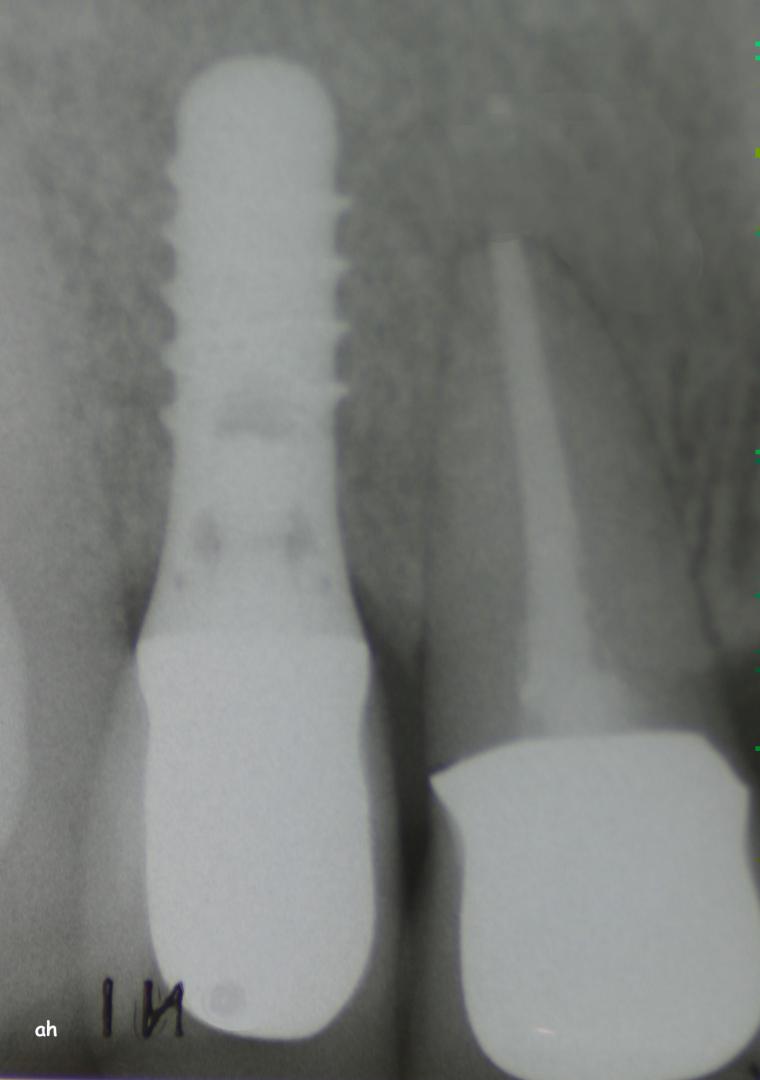

Exemple 12: Ici la pose de deux implants est envisagée, mais la hauteur d'os est insuffisante pour le deuxième implant. Le sinus (qui est une cavité creuse) est à moins de 6 mm de la surface de l'os. Idéalement il faudrait 10 mm d'os.

Exemple 12: Il faut donc relevé le sinus avec une greffe d'os avant de poser l'implant (Sinus lift).

Exemple 12: Les moignons vissés sur les implants 6 mois plus tard.

Exemple 12: Les couronnes en place.